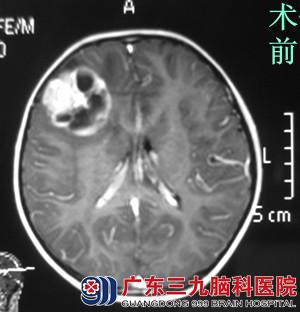

大家七手八脚把小开送往医院,当地医院行头颅CT检查提示右额叶占位。医生告知小开的头上可能长了个肿瘤。小开的父母难以置信,带着他赶往广州一家医院进一步检查,行头颅MR检查,结果提示右侧额叶占位,大小约4.0*4.3*3.7cm,考虑神经节细胞胶质瘤可能性大。小开妈妈苦恼地说:“一个荔枝三把火,没想到这荔枝这么毒的……“

在朋友的联系下,小开的家人找到广东三九脑科医院 综合神经外科(神经外五科)的鲁明主任,鲁主任考虑小开年龄小,手术尽量避免功能障碍,术中唤醒麻醉及电生理监测。完善相关检查后,由鲁明主任主刀,在唤醒麻醉下行右额叶肿瘤切除术,术中导航引导,见灰白色肿瘤组织,质软,边界较清,唤醒患者,患者语言及肢体功能正常,显微镜下完整切除肿瘤,电生理监测未见明显皮层异常放电,术后小开未造成任何的功能障碍,手术顺利结束。术后小开经过专科治疗护理,顺利康复。术后病理结果:中枢神经系统节细胞神经瘤。